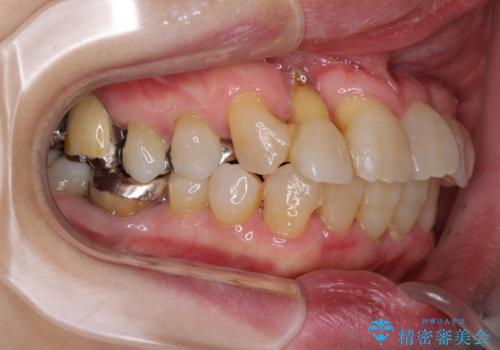

- 歯の欠損や歯肉からの出血などを気にして来院された患者様です。

診査の結果、歯周病であることが分かり、抜歯が必要な歯も見受けられました。

骨造成やインプラント、歯周外科、歯肉移植、矯正など、多くの処置を組み合わせて治療を行うこととしました。

数多くの外科処置を行ったため、治療期間は長期間となりました。

一方、外科処置をしっかりと行ったことで、歯周病の状態は改善され、安定した状態にしあげることができました。